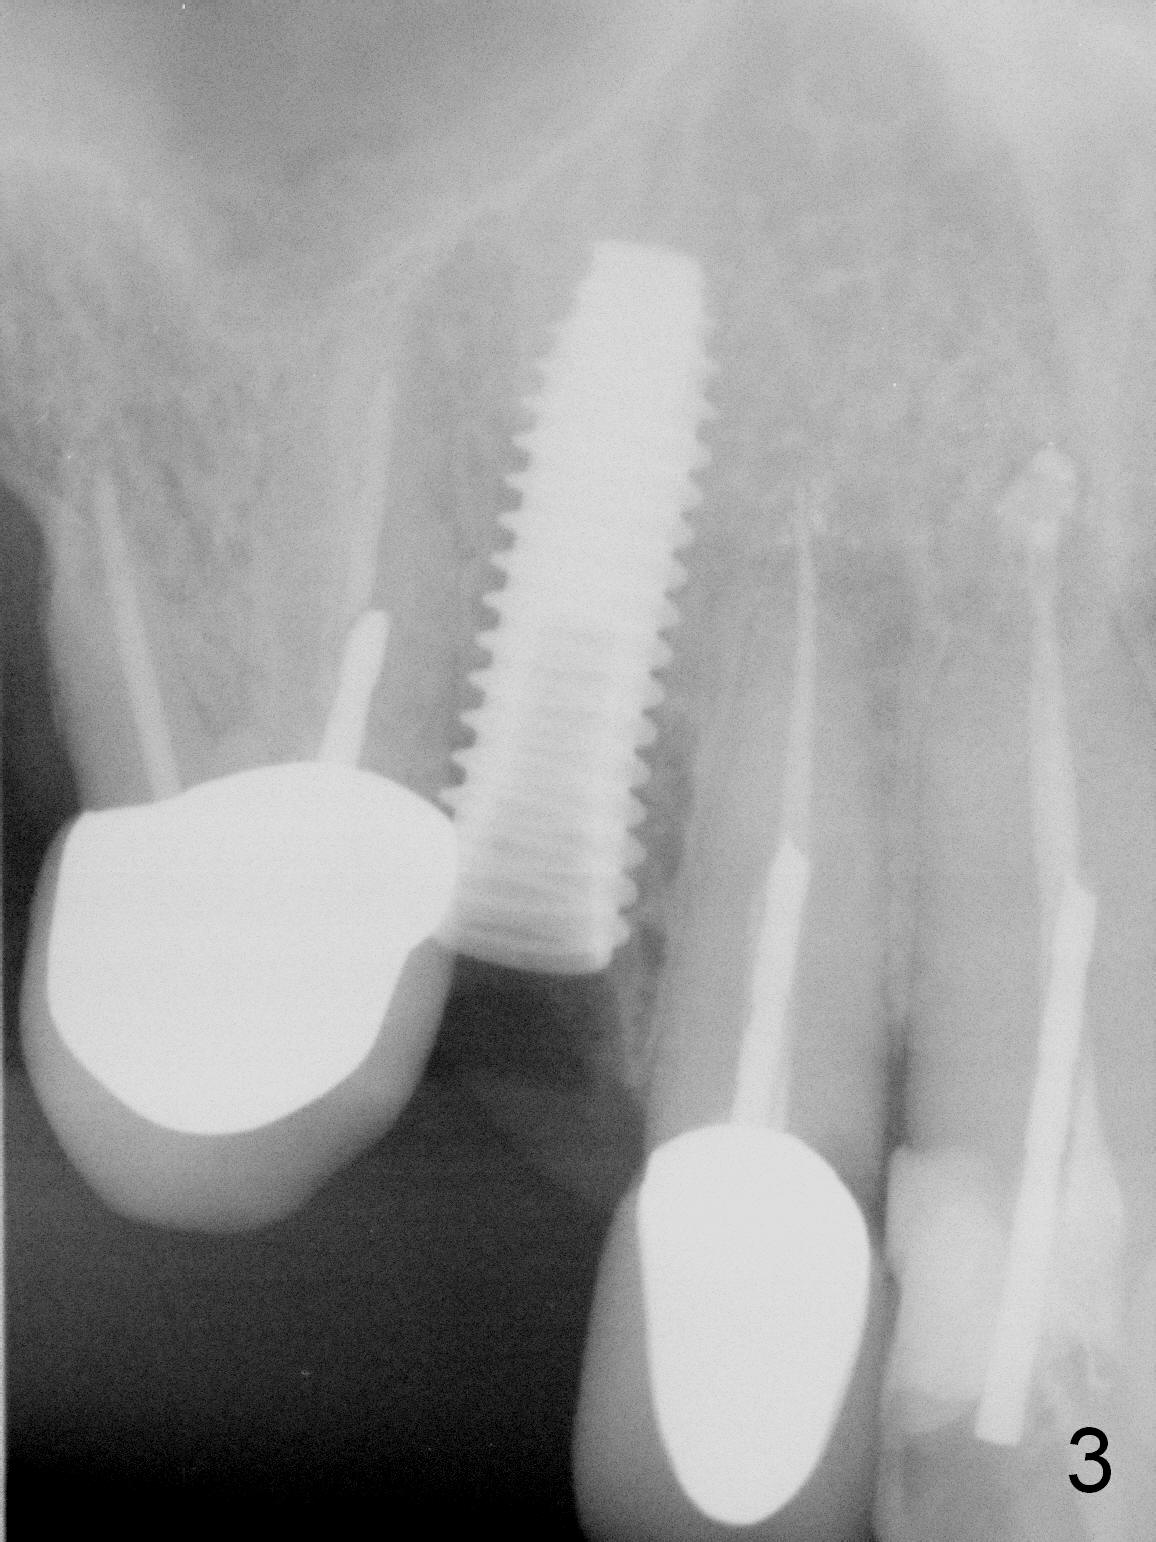

After extraction of the subgingival fractured upper right canine (Fig.1), the buccal plate is found to have been perforated at the apex. the root is measured 5x12 mm. Initial osteotomy with a 2 mm pilot drill shows that the bone is soft (Fig.2). After use of a 3.2 mm drill (underprep, normal drill size (3.7 mm)), a 4.5x15 mm implant is placed with insertion torque > 50 Ncm (Fig.3). The implant is further torqued until the implant plateau is 3 mm apical to the buccal gingival margin; a 5.5x5(3) mm abutment is placed (Fig.4,5 A). Osteogen plug is inserted into the apex of the socket, while the rest of gap is filled with mineralized cortical allograft and Osteogen. An immediate provisional (Fig.5,6 P) is fabricated to keep the graft in place, followed by periodontal dressing (Fig.6).